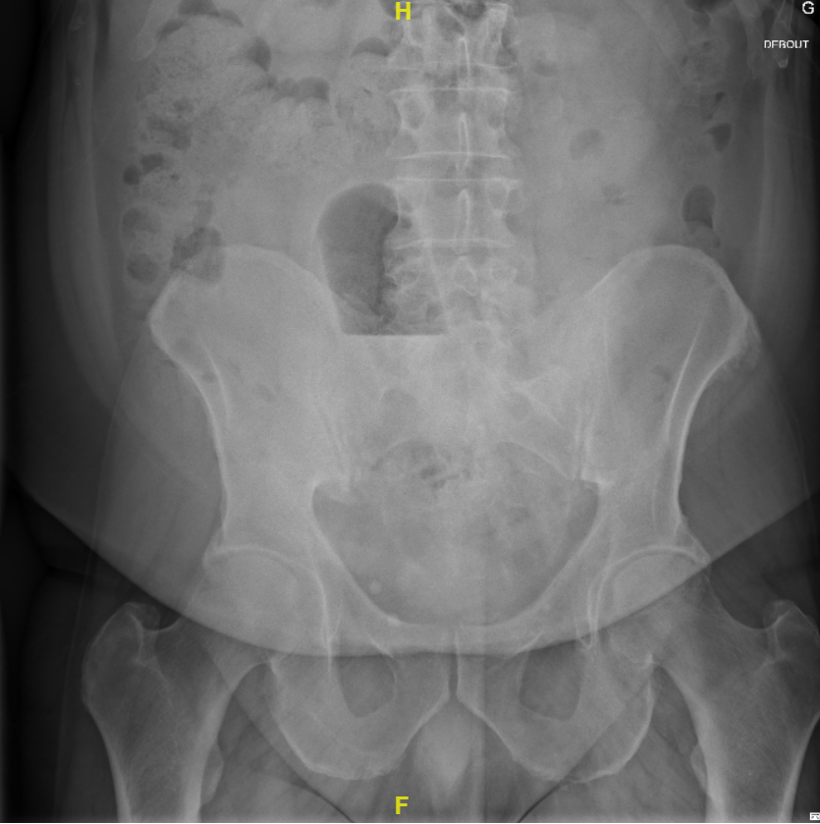

Corps étranger ano-rectal

Un corps étranger au niveau anal et/ou rectal est une urgence ano-rectale au vu du risque de perforation. Selon les sources, les patient·es concerné·es sont majoritairement des hommes (plus de 90%), de tous les âges avec une médiane autour de 45 ans. Les corps étrangers retrouvés sont divers (sex toys, objets en verre, bouteilles aérosols, déodorants, fruits, légumes,...). Le plus souvent, l'insertion d'un corps étranger est volontaire dans le cadre de pratiques sexuelles. On retrouve aussi parfois comme motif la constipation, la dissimulation d'objet, l'insertion accidentelle (souvent évoquée, notamment dans les cas de maladies psychiatriques sous-jacentes) ou par un tiers contre la volonté du patient.

Il existe peu d’études sur le traitement des corps étrangers dans l’anus/rectum et la littérature se compose principalement de case reports. La plupart du temps, en absence de péritonisme abdominal, l’objet peut être retiré aux urgences ou par endoscopie, sans anesthésie générale. Mais, comme ce fut le cas pour ce patient (échec de retrait aux urgences et par colonoscopie par les gastro-entérologues), une intervention sous anesthésie générale est parfois nécessaire. Ici, une laparotomie a dû être effectuée pour retirer l’objet.